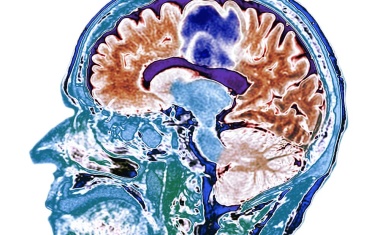

Ein Einsatzgebiet von Künstlicher Intelligenz (KI) ist die Medizin, vor allem die Diagnostik. So können beispielsweise Scans mit Hilfe von Algorithmen maschinell ausgewertet werden.